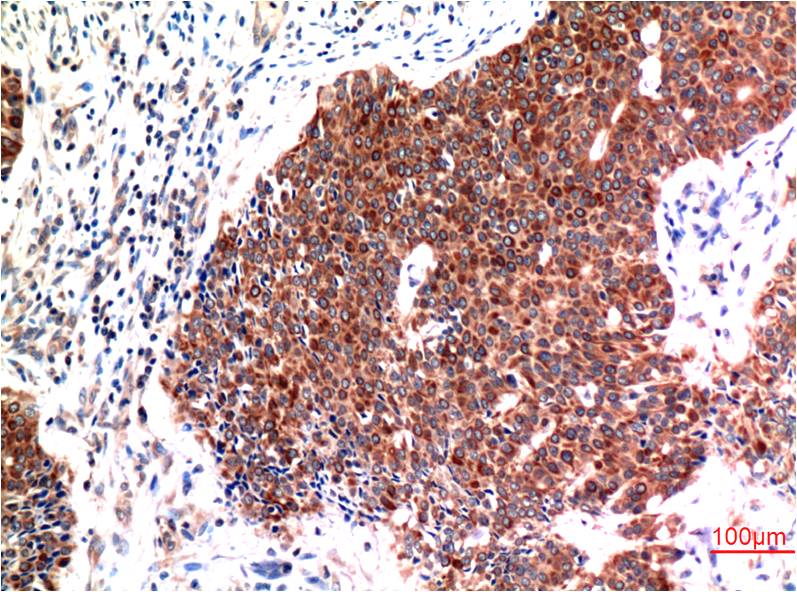

Immunohistochemical analysis of paraffin-embedded Human Breast Carcinoma Tissue using?Beclin-1(EM1304)Mouse mAb diluted at 1:200.